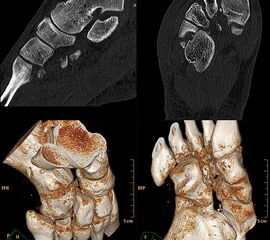

Bei Verdacht auf eine Lisfranc-Verletzung sollte daher die Indikation zur Computertomographie (CT) mit multiplanaren Rekonstruktionen großzügig gestellt werden. Hier können auch diskrete Dislokationen und kleine Fragmente gut dargestellt werden. Auch bei Nachweis einer Lisfranc-Verletzung sollte stets ein CT zur Suche nach Begleitverletzungen sowie zur Planung der weiteren Therapie angefertigt werden 9751164 (Richter 2007).

Zum Lesen der Bildbeschreibung und zur Vollansicht bitte das Bild anklicken.